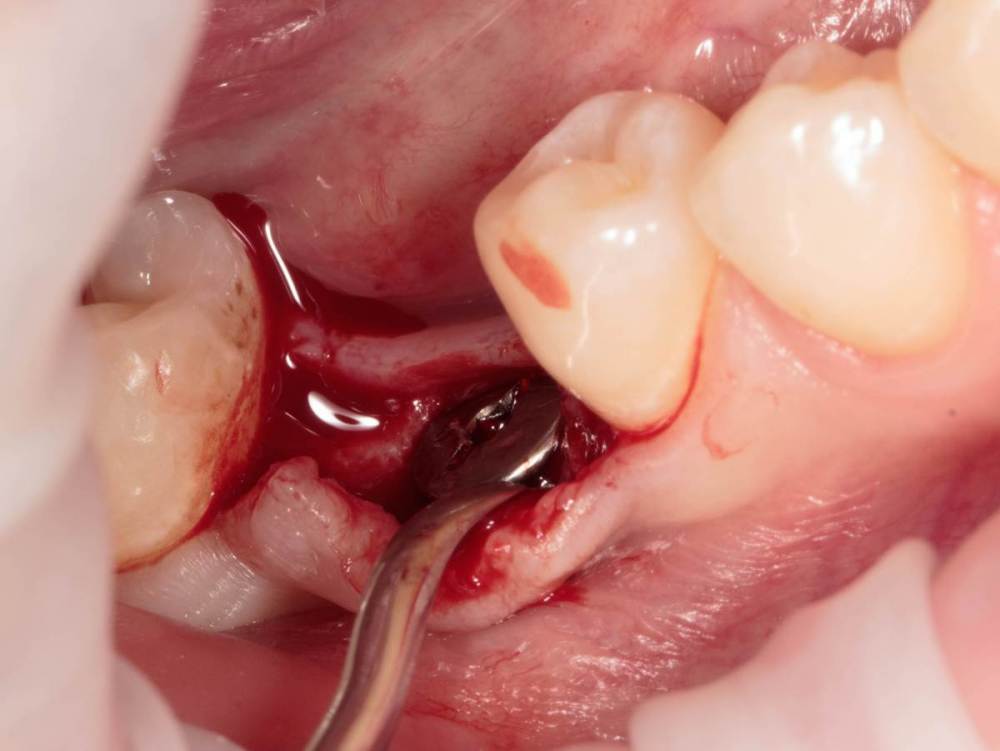

Женька Опубликовано 19 августа, 2023 Поделиться Опубликовано 19 августа, 2023 ?️. Поймал себя на мысли, что испытываю проблемы с ушиванием+ССТ на формике. А именно-не устраивает результат "прирощённой" десны. Вроде на ушивании есть + к объёму, а на протезировании "яма" вестибулярно лишь немного уменьшилась. Подскажите, как лоскут формировать так, чтобы в слоёном пироге имплантат-формик-сст оставался объём слизистой, а не таял. Подумал, что может стоит при имплантации сразу формировать асл. А в кейсе я снова "согрешил" и поставил ультра-низкий формик. В этот раз без всяких послаблений лоскута и натяжения, кмк. Ссылка на комментарий

Женька Опубликовано 21 августа, 2023 Автор Поделиться Опубликовано 21 августа, 2023 @annda вот тут всё по одному месту пошло в попытке закрыть эти низкие фдм. Ссылка на комментарий

Женька Опубликовано 21 августа, 2023 Автор Поделиться Опубликовано 21 августа, 2023 @annda да не, там всё стык в стык пассивно ушилось. скорее это потому, что "ножка" в воздухе просто висела по сути, прикрепиться не к чему, вот и до свидания Ссылка на комментарий